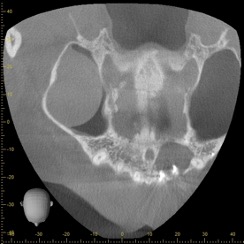

右下と左下の欠損部にはインプラント治療をご希望されました。また上あごの前歯が割れており、膿がたまって骨が大きく溶けてしまっていたため、抜歯を行いブリッジ治療を施しました。

【術前の前歯のCT写真】↓骨が大きく溶けているのがわかります。